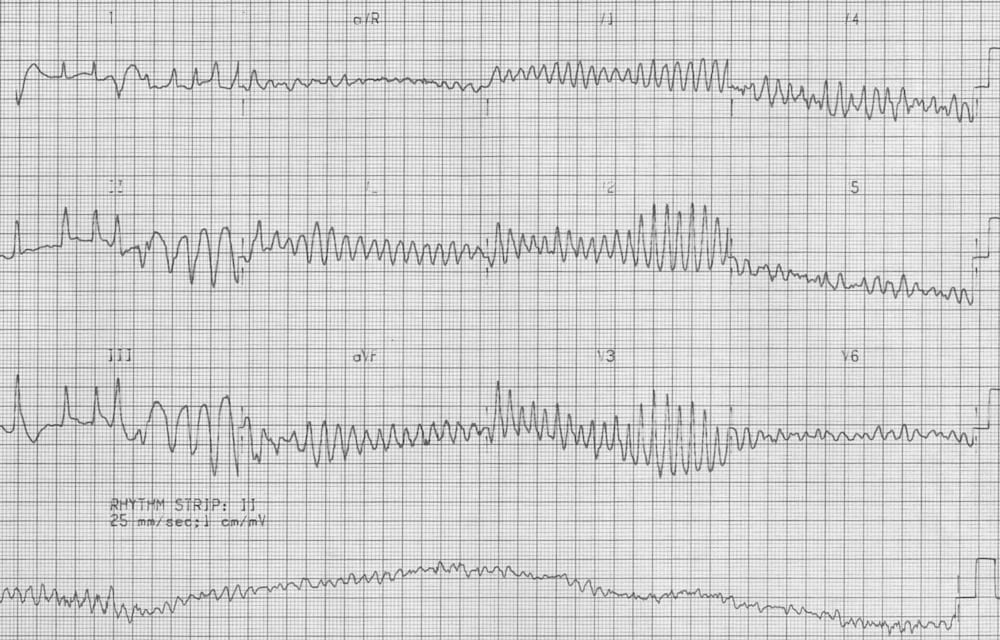

ECG 2 is being taken as the patient becomes unconscious on the trolley

The second ECG shows: